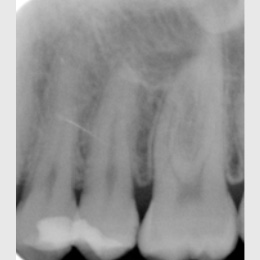

Fallbeispiel: Revision 45 nach Wurzelspitzenresektion (WSR) Recall 30 Monate

Auch Zähne, die bereits eine Wurzelspitzenresektion erhalten haben, können erfolgreich mit einer Revision behandelt werden.